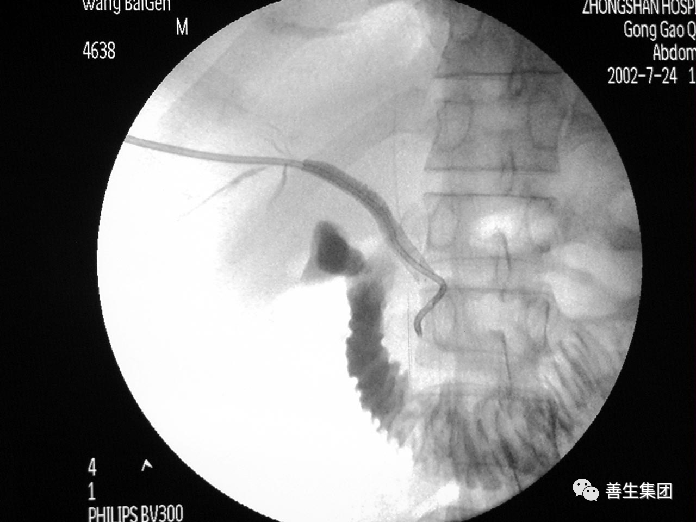

高位梗阻PTC示肝门部梗阻,左右肝管分别受侵犯

高位梗阻胆管癌患者

穿刺右肝管分别穿刺左右肝管,Y型放置2枚支架型内支架